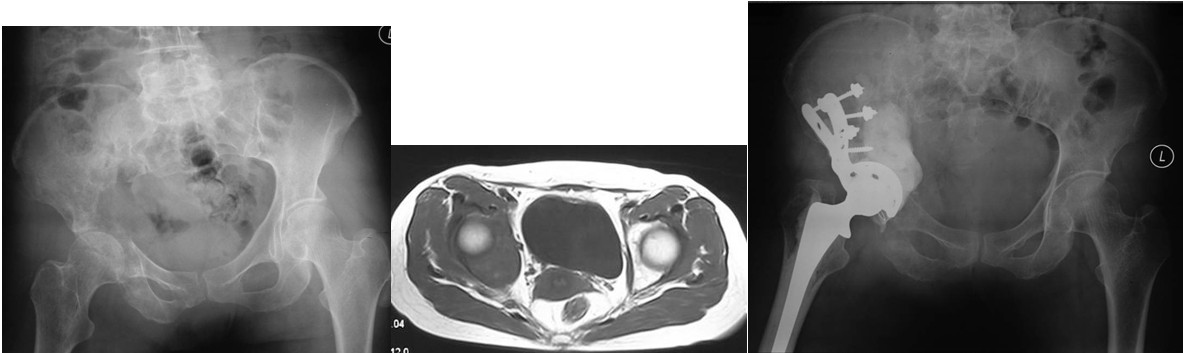

本组病例中不同部位髋臼转移癌的手术方式(图1):I型:髋臼下壁骨破坏、上壁及内、外侧壁完整, 采用肿瘤刮除、普通水泥型全髋置换术。II型:髋臼内、外侧壁破坏,上壁骨质完整, 采用带翼网杯+水泥型全髋置换术。 III型:髋臼上壁及内、外侧壁均破坏,采用肿瘤刮除后、骨水泥填充髋臼上壁骨缺损,带翼网杯+水泥型全髋或组合式人工半骨盆。IV型:孤立性骨盆转移, 以治愈为目的, 采用肿瘤整块切除,组合式人工半盆置换术。

Ⅱ型:髋臼内侧壁缺损,而周边骨质完好。采用普通髋臼会导致假体及骨水泥早期向内侧移位。对于这种情况,应采用特殊设计的带翼髋臼网杯将应力引至髋臼缘。安装时在保持髋臼假体正确解剖位置的同时需注意将网杯的翼放置在完整的髋臼缘,因为部分髋臼边缘可能存在破坏。可以采用后外侧入路,通常无需大转子截骨,尽量使用长颈人工头,以防止粗隆部撞击网杯延伸缘。股骨粗隆部,股骨干有潜在骨折时,应使用长柄髓内针的人工股骨头。术后第一天病人即可下地负重活动。

Ⅲ型:髋臼内壁、顶部及外侧壁均破坏。仅使用带翼网杯的全髋假体是不够的。在这种情况下,需要在骨盆缺损处放置数根斯氏针以便于将位于解剖位置的髋臼假体所承受的应力传导至脊柱(1-3)。在大多数髋臼周围破坏广泛的病例,需要采用扩大的髂股骨切口入路,以便于探查骨盆内外侧区域。在显露清楚后,自髋臼缺损处沿残留的正常髂骨向骶髂关节方向钻入2-3根斯氏针,并越过关节达到骶骨。应采用较粗的斯氏针,术中还需要X线监测以保证斯氏针的位置。在钻入斯氏针的同时,应用手指触摸坐骨切迹,以保证斯氏针的方向,防止其穿入骨盆内壁。当髋臼缺损较大时,还可以自前部髂嵴向前柱的耻骨及后柱的坐骨钻入更多的斯氏针做进一步的加强。在髋臼假体顶部切断斯氏针,并安装带翼网杯,在髋臼深部可以用金属钛网加强骨水泥固定。术后病人可全部负重行走,但需置患肢外展中立位约4周时间以防止脱位。也有采用马鞍式假体置换的报道, Benevenia等对20例髋臼III型转移瘤患者进行了马鞍假体置换,术后MSTS 93评分平均16.6分,多数病人可以扶拐行走(5)。对于髋臼上壁及内、外侧壁均破坏的HarringtonIII型患者,本组病例中,有7例患者采用了肿瘤刮除后、于骶髂关节处植入3-4枚斯氏针, 骨水泥填充髋臼上壁骨缺损,水泥型全髋重建髋关节。其中,有2例患者出现下地后髋部痛疼,负重时髋部不稳定。考虑为负重时骶骨内斯氏针承受较大剪力, 出现髋关节不稳。因此,在本组病例中,我们对4例Ⅲ型患者实施了整块切除、可调式人工半骨盆置换术。术后6周患者可以扶拐下地行走。平均MSTS93评分为23.3分。

Ⅳ型:为了达到治愈而需要进行整块的髋臼切除。对于部分单一髋臼转移的病例,以及髋臼周围骨质破坏范围较大的病变,在广泛切除肿瘤后,重建髋关节(内半盆切除)有时较为困难。在这些病例,可以选择马鞍式假体。这种方法最开始用于全髋关节置换术后的骨缺损,后来也用于原发或转移性髋臼肿瘤的治疗。也可以选用带有固定翼,能固定于残存髂骨和耻骨支的定制型髋臼假体(7-9)。这种假体制作前通常需要进行CT模拟重建设计。固定方式常用螺丝钉和骨水泥。有时想要应用定制型假体达到理想的固定位置较为困难。对于骨盆环的完整性重建,纵向稳定是极其重要的,同时要考虑人工假体在术中的可操作性。定制型骨盆假体为非组配式,其髂骨固定螺钉是单轴向的,不能根据术中截骨情况调整假体,固定也不够牢固。 我们设计使用的可调式半骨盆假体,其髂骨固定钉改为双轴向或多轴向固定,假体与骨之间的界面为垂直压力、而非剪力,增加了稳定性,同时可以根据髂骨截骨的高度选择颈长的臼杯,利于安装和保持骨盆平衡(10)。组配式骨盆假体还考虑到骨盆纵向和侧方的稳定因素, 尽量达到恢复骨盆环连续性和稳定性的目的。对于髂骨区和髋臼上缘的骨缺损重建,钉棒系统简单,易于操作,但固定钉在骨内的应力较大,容易在负重的情况下对骨质产生切割,尤其骨质疏松的病人固定更加不稳,因此需用骨水泥加强。由于组配式人工骨盆是一个组合装置,因而体积较小,便于软组织覆盖,伤口感染率大大下降。

图3,女,55岁,肺癌髋臼转移, Harrington II型

图4,女,52岁,乳腺癌髋臼转移, Harrington III型

图5,男,69岁,肾癌髋臼转移, Harrington IV型